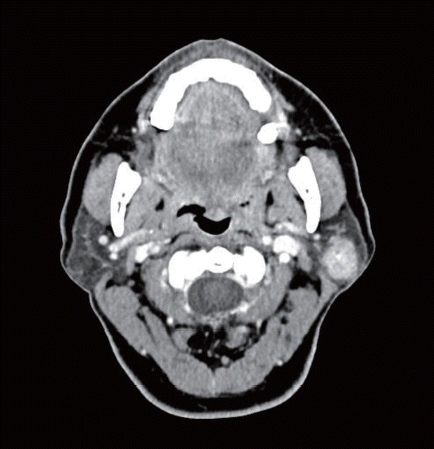

58세 여환에서 좌측 이하선 천엽에 국한된 2 cm 고형성 종괴가 관찰되었다. 이하선 천엽절제술 시행 후 조직검사상 선방세포암종(acinic cell carcinoma)으로 확인되었다. 절제연에서 종양은 관찰되지 않았으며 영상검사상 전이로 의심되는 소견은 관찰되지 않았다. 향후 치료를 위한 적절한 조치는?

kjorl-68-12-548i1.tif